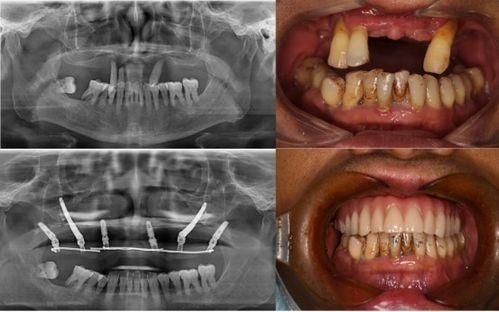

话说那天,佛山某口腔医院的一则视频在网络上迅速走红。视频中,一位患者痛得满头大汗,而医生却似乎并不在意,还在继续操作。这一幕被患者家属用手机记录下来,随后上传到了网上,瞬间引发了网友们的热议。

视频中,患者躺在手术台上,面部表情痛苦,嘴里插着牙具。医生则在一旁操作,似乎并没有注意到患者的痛苦。更有甚者,视频中还出现了医生在手术过程中玩手机的情况。这一幕让不少网友纷纷表示:“这医生也太不专业了吧!”